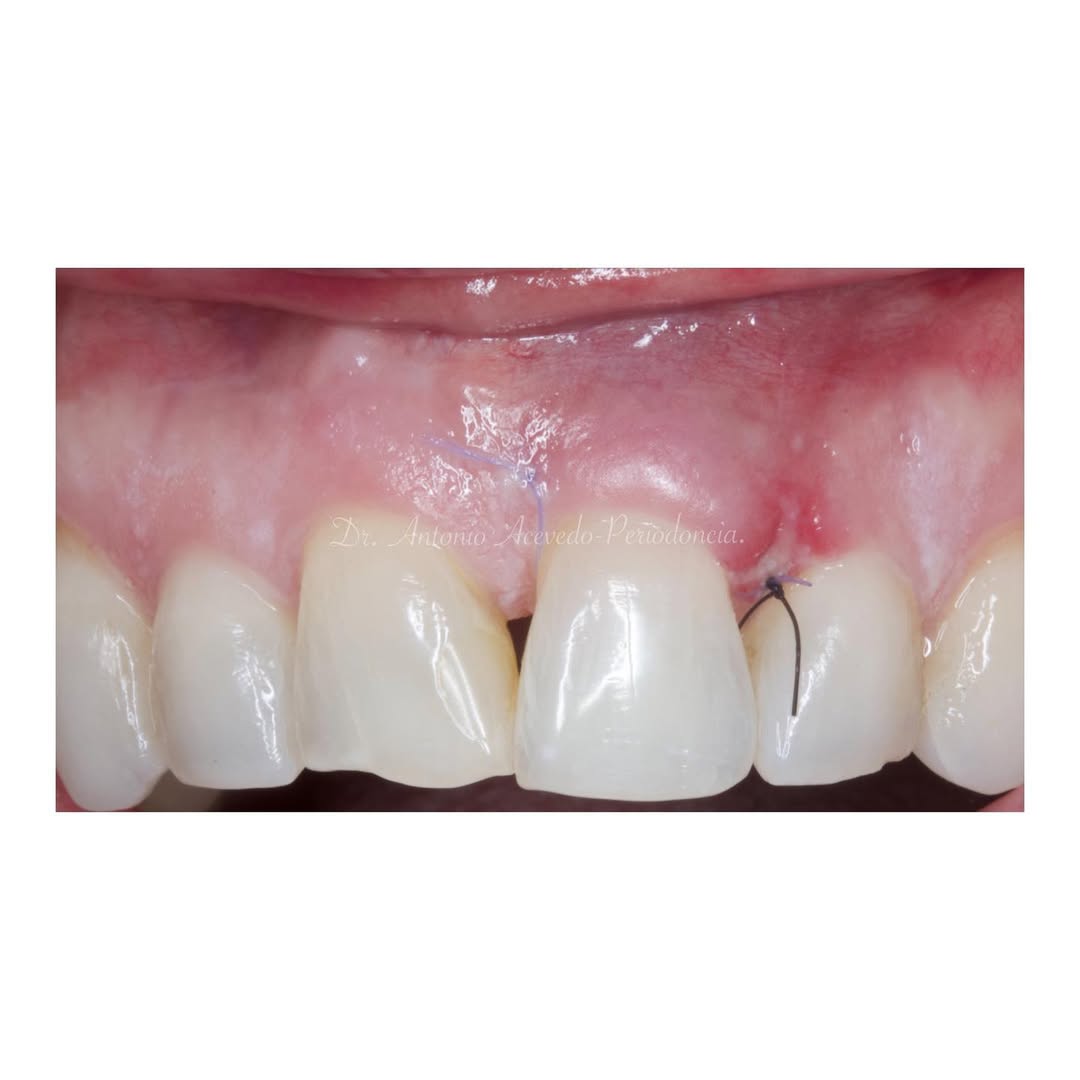

Durante una mañana, asistirás a una Cirugía Mucogingival de recubrimiento radicular de una recesión unitaria en 31 con frenillo asociado. Gracias al uso del microscopio y a la proyección en tiempo real en pantalla, verás exactamente lo mismo que veo yo durante la cirugía, sin tener que estar